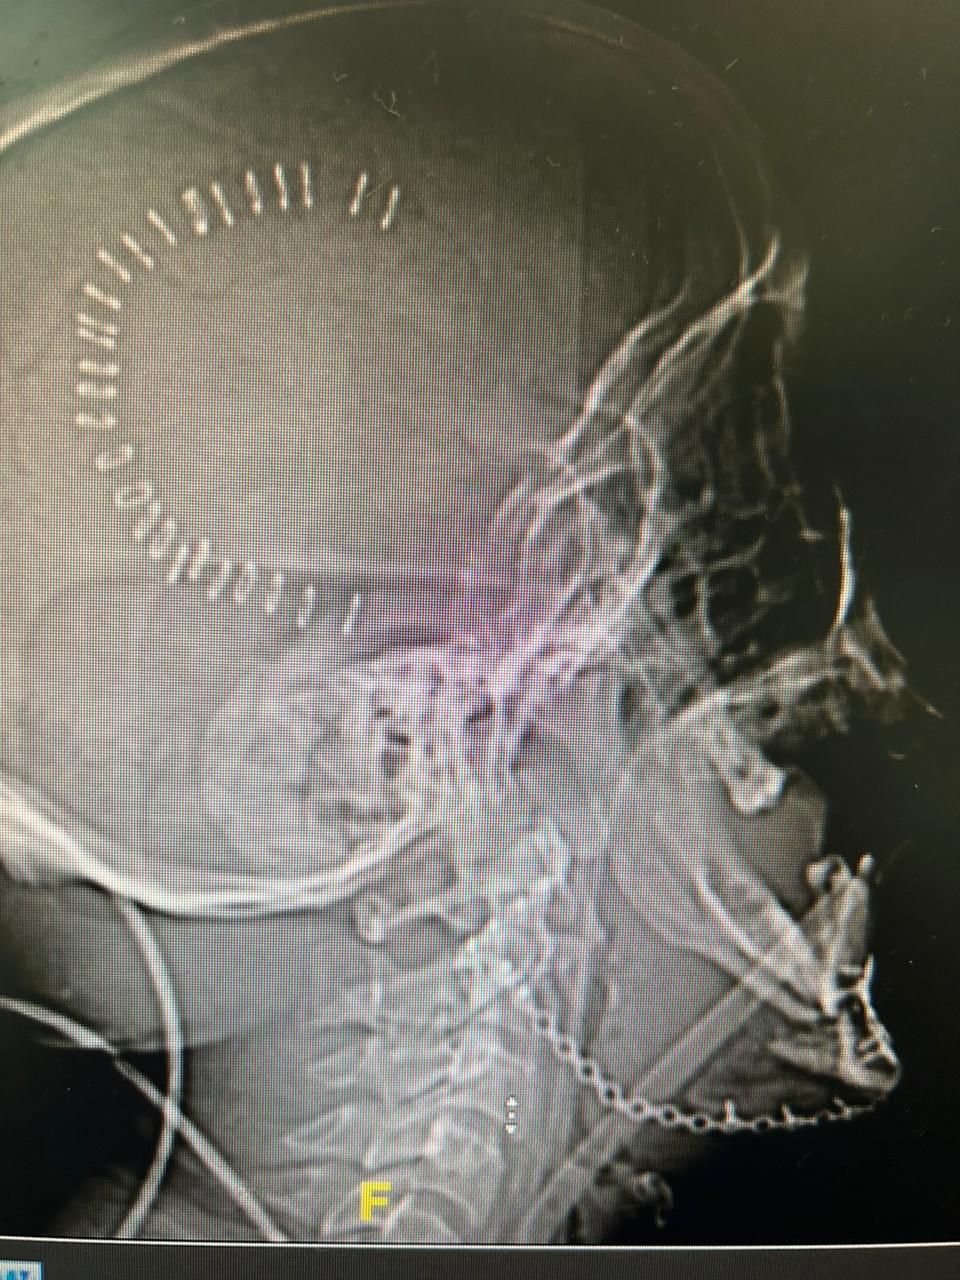

وأفادت “صحة جدة”، بأن قسم الطوارئ بمجمع الملك عبدالله الطبي، استقبل مصاباً إثر تعرُّضه لضربة بآلة حادة في الجهة اليمنى من الوجه أحدثت له تشوّهات كبيرة في الوجه وتهتكاً في أنسجة وعظمة الفك السفلي، وتقرر إجراء عمليتين جراحيتين منفصلتين لإعادة ترميم الفك المتهشم في الجهة اليمنى من الوجه وتركيب بديل لعظمة الفك.

وقال الفريق الطبي المشرف على علاج الحالة، أنه تم تقديم الإسعافات الأولية فور وصول الحالة لقسم الطوارئ وعمل الفحوصات الطبية اللازمة التي بيّنت وجود تهتك شديد بأنسجة وعظمة الفك السفلي؛ حيث تمّت دراسة الحالة مع الفرق الطبية المختصة وتقرر إجراء عمليتين منفصلتين.

وأضاف الفريق: “أجريت العملية الأولى عن طريق فريق طبي متخصّص في عمليات جراحة الوجه والفكين بعد عملية عاجلة دقيقة؛ نظراً لخطورة الحالة، استمرت 6 ساعات لإيقاف النزيف وإجراء ترميم مبدئي للجهة اليمنى من الوجه دون حدوث أي مضاعفاتٍ؛ ليتم نقل المريض للعناية المركزة لحين استقرار الحالة”.

وتابع: “من ثم البدء بعملية جراحية دقيقة ثانية تمّ فيها تركيب بديل لعظمة فك الجهة اليمنى، في عملية استغرقت 3 ساعات؛ ليتم نقل المريض بعدها لغرف التنويم لعمل المتابعات العلاجية مع الفرق التمريضية المتخصصة والتخصصات الأخرى إلى أن استقرت حالته الصحية وخروجه بالسلامة بإذن الله”.